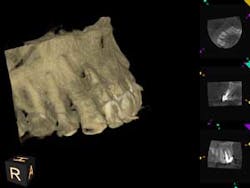

A 60-year-old male patient presented with a buccal swelling in the maxillary left anterior. Clinically the patient had a three-unit bridge connecting Nos. 7–9 (figure 1). The patient was happy with the esthetics and wanted to save his natural dentition. The recommendation was made to take a narrow-field CBCT scan to evaluate No. 7 in three dimensions. The CBCT scan showed that the apical disease had led to root resorption at the apical third of tooth No. 7 on the distal root surface (figure 2). This was invaluable information that allowed me to make the best approach to the root surface while keeping the osteotomy as small as possible. It also allowed me to have a three-dimensional view of No. 7 before even beginning the surgery, which helped to aid in proper root resection to conserve as much sound tooth structure as possible.

After root resection, root end prep and the placement of biologically compatible root end filling, the osteotomy was grafted (figure 3). Because of the size of the apical disease, along with the large cast post and the resorption, traditional nonsurgical retreatment was not a viable option for long-term success. With the aid of the CBCT imaging, it was already noted where the root end filling needed to be placed not only to seal the distal defect but to seal the true apical terminus.